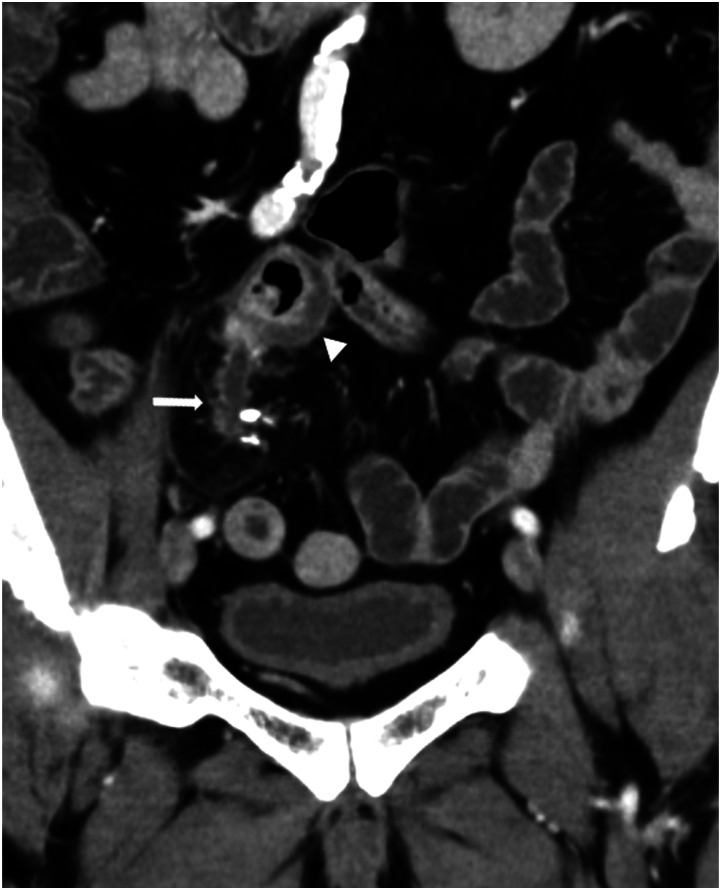

Ectopic pancreas within the mesentery is rare. In this case report, a 61-year-old man with an ectopic pancreas within the jejunal mesentery for over 20 years developed chronic pancreatitis that progressed to acute exacerbation. Our computed tomography (CT) performed for acute abdomen assessment suggested acute appendicitis or Meckel's diverticulitis. However, a CT scan taken 20 years ago revealed a structure indicative of an ectopic pancreas in the mesentery, and further imaging findings taken 10 and 4 years ago confirmed progression to chronic pancreatitis. Furthermore, we found a pancreatic stone confined in the luminal structure that corresponded to the main pancreatic duct; this stone eventually caused acute exacerbation. In summary, we report a case of mesenteric ectopic pancreas that showed typical findings of progression and acute exacerbation of chronic pancreatitis on CT.